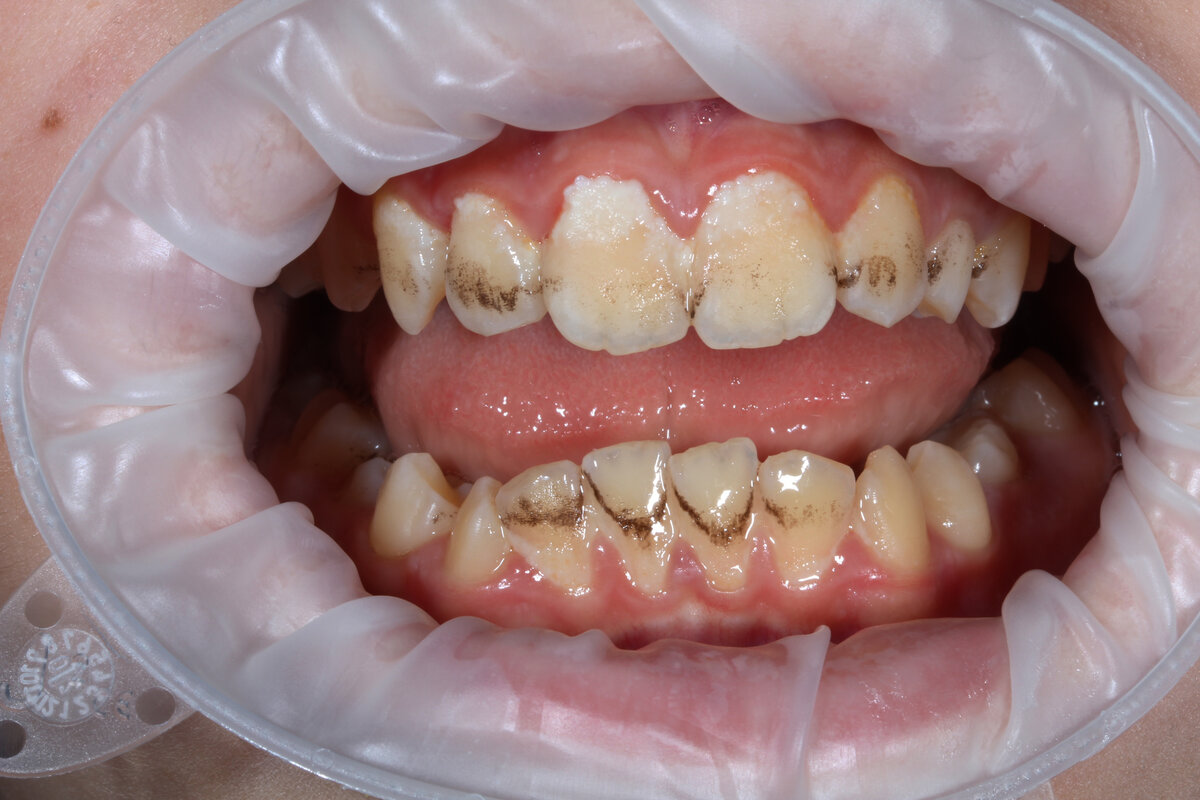

Почему почернели зубы

Не стоит думать, что почернение зуба – это всего лишь эстетическая проблема, которая делает улыбку менее привлекательной. На самом деле, потемнение зуба или нескольких может свидетельствовать о наличии не только кариеса, но и более сложных заболеваний зубов.

Естественный оттенок зубов зависит вовсе не от качества и цвета эмали. На самом деле зуб приобретает свой оттенок благодаря цвету дентина, который просвечивается через прозрачность эмали. И чем светлее дентин, тем светлее и улыбка в целом. Процесс приобретения #почернения зубов, как правило, происходит постепенно, иногда практически не заметно.

При обнаружении темных #пятен или точек на зубе, следует пересмотреть качество гигиены полости рта. Возможно, неправильно подобранная #зубная паста, щетка или другие аксессуары, а также некачественный процесс чистки зубов стали причиной появления такого дефекта. Также следует брать во внимание, что иногда зубы темнеют после употребления в пищу красящих продуктов.

Но существует ряд других причин и факторов, которые вызывают почернение зуба или нескольких зубных единиц:

• Черные пятна на поверхности зубов могут свидетельствовать о #возникшем кариозном поражении.